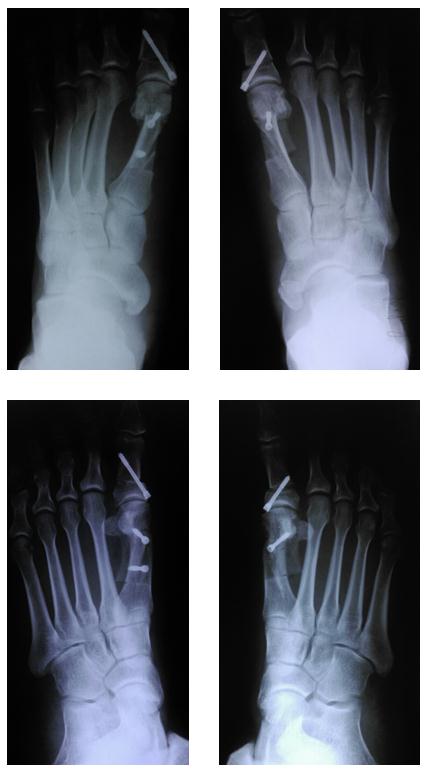

Рентген после операции Hallux valgus